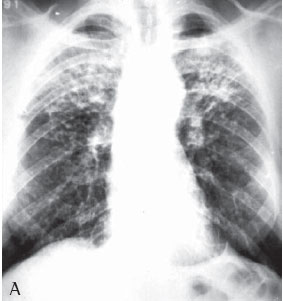

Quanto à classificação radiológica das grandes opacidades na radiografia de tórax verificou-se que: 23 pacientes apresentaram grande opacidade do tipo A (30,7%), 25 do tipo B (33,3%) e 27 do tipo C (36%) (Figuras 1A e 1B). Dos casos analisados, 74 apresentaram massas conglomeradas bilaterais, e apenas 1 apresentou lesão unilateral (Figuras 2A e 2B).

Mais da metade dos pacientes com silicose complicada apresentou na radiografia de tórax grandes opacidades dos tipos B e C, o que denota a gravidade da doença nestes pacientes.